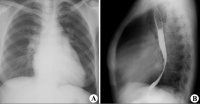

(一)X线检查:最早的改变是左心缘的左心房弧度明显,肺动脉主干突出,肺静脉增宽,右前斜位钡剂透视可见扩张的左心房压迫食道。病变严重时,左心房和右心室明显增大,后前位片示心影右缘呈双重阴影,肺门阴影加深,主动脉弓较小。左心室一般不大。当左心房压力达2.7kPa(20mmHg)时,中下肺可见KerleyB线。长期肺淤血后含铁血黄素沉积,双下肺野可出现散在的点状阴影。老年患者常有二尖瓣钙化,青壮年亦不少见。